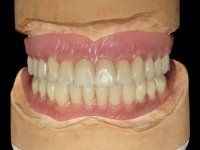

After the implant impressions with silicones, the working model was built with artificial gingiva. Then, the dental technician fabricates the record bases with the wax rims with the particularity of being screwed on the implants to achieve a proper stability. The correct vertical dimension and the lip support were determined with record bases screwed over the implants. To validate these records we have also used the “Individualized Geometric Analysis of Facial Harmony (AGIHF)” by Professor Carlos Silva.

Then, the teeth were mounted in the screwed record bases and function and aesthetics were clinically evaluated. After these evaluations, the dental technician develops silicone walls that guide the fabrication of the milled bars. The precise passive fit of the bars was checked clinically and with radiographs. Then, a pick-up impression with an individualized tray was done to achieve a functional impression of the soft-tissues.

The overdentures with a metallic framework were fabricated over the bars, according to the silicone walls previously made. Before finishing the dentures, a new functional and aesthetic evaluation of the teeth was done, together with a new jet-bite registration to allow small occlusal adjustments.